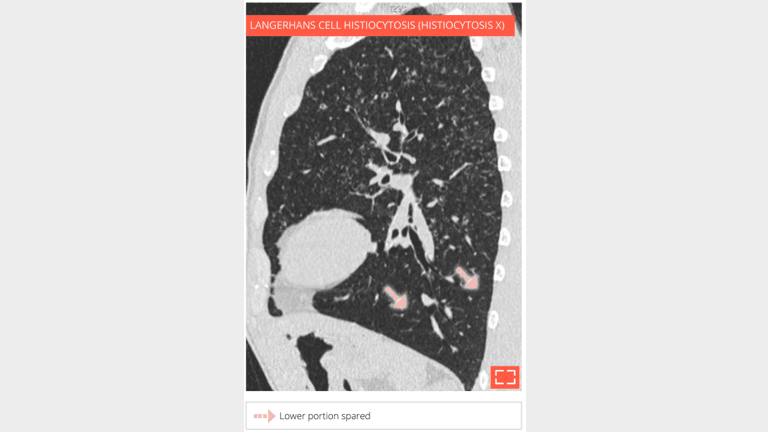

Sagittal reformation in the same patient shows the upper lobe distribution of parenchymal abnormalities